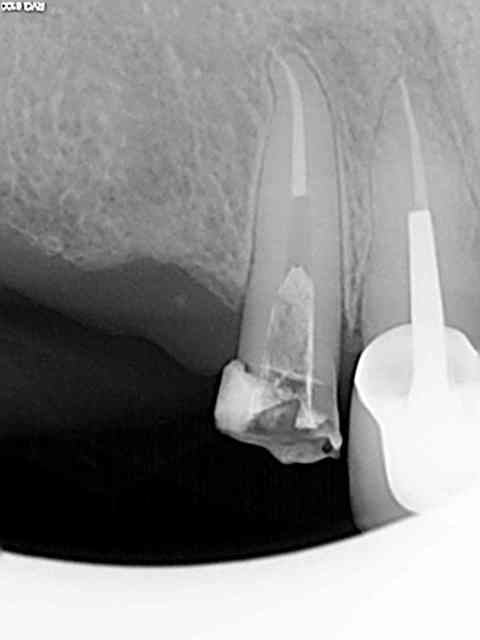

Exemple sur cette 12 tout à l'heure, 1h 30 de rdv terminé en 1h et encore j'ai un peu "tâtonné" pour trouver la pulpe. Toujours pas de cathétérisme manuel of course sinon j'y serais encore.)))))